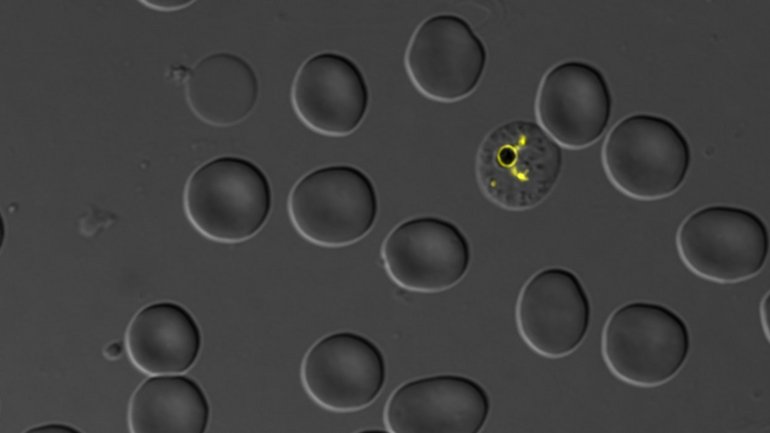

Plasmodium falciparum parasite and its digestive vacuole (yellow)